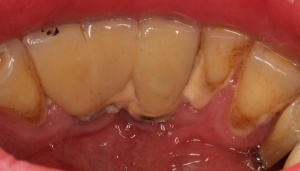

Ähnlich wie eine Entzündung am natürlichen Zahn in Form einer Parodontitis auftreten kann, kann eine Entzündung periimplantär auftreten. Sie geht mit einem periimplantären Knochenabbau einher. Dieser kann schubweise oder auch kontinuierlich voranschreiten. Der entscheidende Unterschied zwischen Zahn und Implantat ist das fehlende parodontale Ligament periimplantär. Damit ist die Immunabwehr reduziert. Das periimplantäre Gewebe hat einen höheren Kollagenanteil bei reduzierter Anzahl von Blutgefäßen.

In der prächirurgischen Phase muss ein besonderes Augenmerk auf die prognostische Einschätzung der parodontalen und dentalen Situation gelegt werden. Dabei ist insbesondere auf die allgemeinmedizinische und spezielle dentale Anamnese zu achten. Bornstein et al. (2009) untersuchten den Einfluss von Allgemeinerkrankungen auf die Periimplantitis. Unter anderem Safi et al. (2009) wiesen auf die Bedeutung einer Parodontitishistorie hin. Aber auch die Lebensgewohnheiten des Patienten haben einen entscheidenden Einfluss (Tabakkonsum, ungenügende Mundhygiene, fehlende Nachsorge [Heitz – Mayfield & Huynh – Ba 2009]) (Abb. 3).

Auf die Reinigungsfähigkeit mit Zahnseide, Super Floss® und/oder Zahnzwischenraumbürstchen ist zu achten. Deren Anwendung ist dem Patienten im Mund zu demonstrieren und von diesem nachzumachen. Im Rahmen der unterstützenden Parodontitistherapie (UPT) und des Implantatrecalls ist auf Schwachstellen hinzuweisen und erneut zu demonstrieren (Abb. 9 a-d).